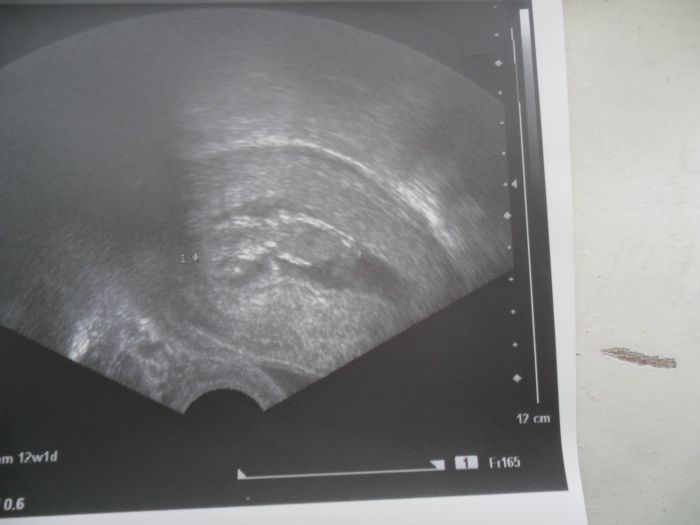

. Já bych měla být v 9 týdnu, ale vůbec teda netuším jak to počítáte, protože tu hodně uvádíte 6+2tt atd. Já byla na prvním ultrazvuku 24.11. a tam mi řekli 7 týden (ult. v příloze). Některé tu píše o nevolnostech a jiné, že je nemáte. Já měla nevolnosti akorád 14 dní, ale to jsem ještě nevěděla, že jsem těhotná. Prsa mně naštěstí už přestaly bolet a nevolnostma ted taky netrpím.

[60689] Teď už ho vidím :-)..taky krásné..a kolikátý týden tu jsi..7 tt?..vypadá oprosti měmu větší :-)..aůle bude to taky možná rozlišením a typem ultrazvuku :-)

Jj, na fotečce je to asi 7 týden (8mm), ve čtvrtek jdu znova, to už by měl být devátý tak uvidím co mi řekne